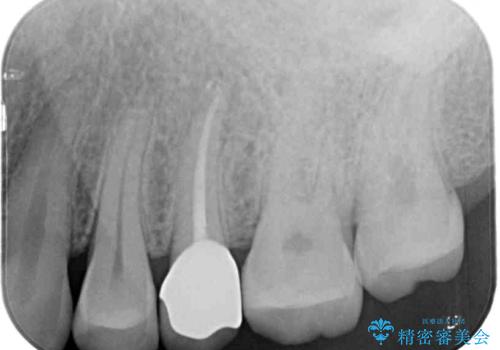

診査の結果、既に歯の神経は失活しており、レントゲンより根尖部に病変を認めました。

補綴後数ヶ月経過しレントゲンを撮影したところ、根尖周辺の病変が消退してきていることが確認できました。